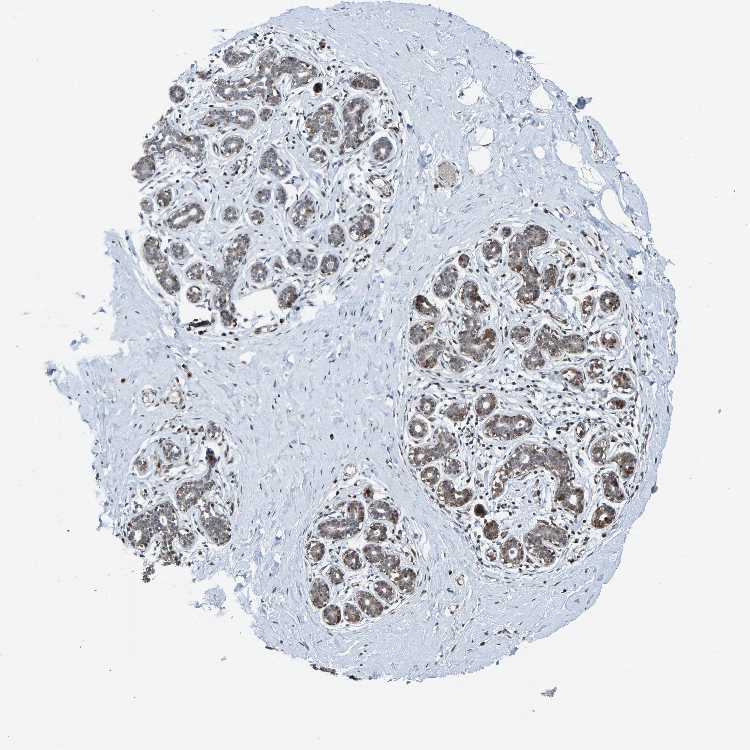

BREAST - Antibody stainingi

Antibody staining in the annotated cell types in the current human tissue is reported as not detected, low, medium, or high, based on conventional immunohistochemistry profiling in selected tissues. This score is based on the combination of the staining intensity and fraction of stained cells.

Each image is clickable and will lead to virtual microscopy that enables deeper exploration of all samples and also displays staining intensity scores, fraction scores and subcellular localization as well as patient and tissue information for each sample.

Antibody HPA023128Antibody HPA023526

Adipocytes LowHigh

Glandular cells LowHigh

Myoepithelial cells LowHigh